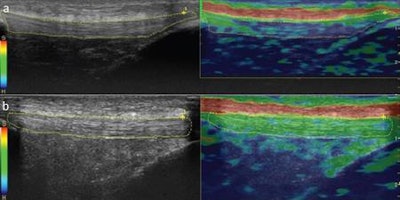

Real-time ultrasound elastography was also performed on the same regions to calculate strain ratio measurements. The scanner's software calculated the strain ratio measurements, coded the tissue strain in the selected region of interest on a scale between 1 (softest tissue, greatest strain) and 6 (hardest tissue, no strain), and then color-coded tendons based on elastographic patterns at the three measurement sites (grade 1, blue: hardest tissue; grade 2, blue/green: hard tissue; and grade 3, green: intermediate tissue).

There were also three additional color-coded subgrades -- subgrade a, no red coloring: homogeneous; subgrade b, parallel red stripes along the length of the tendon: relatively homogenous; and subgrade c, patchy distribution of color codes on the dominant tendon pattern: heterogeneous.

All three areas of the patellar and Achilles tendons were significantly thinner in the smoking group, the researchers found.

In addition, the smoking group also had significantly lower strain ratio measurements than those in the nonsmoking group, indicating that the tendons were harder.